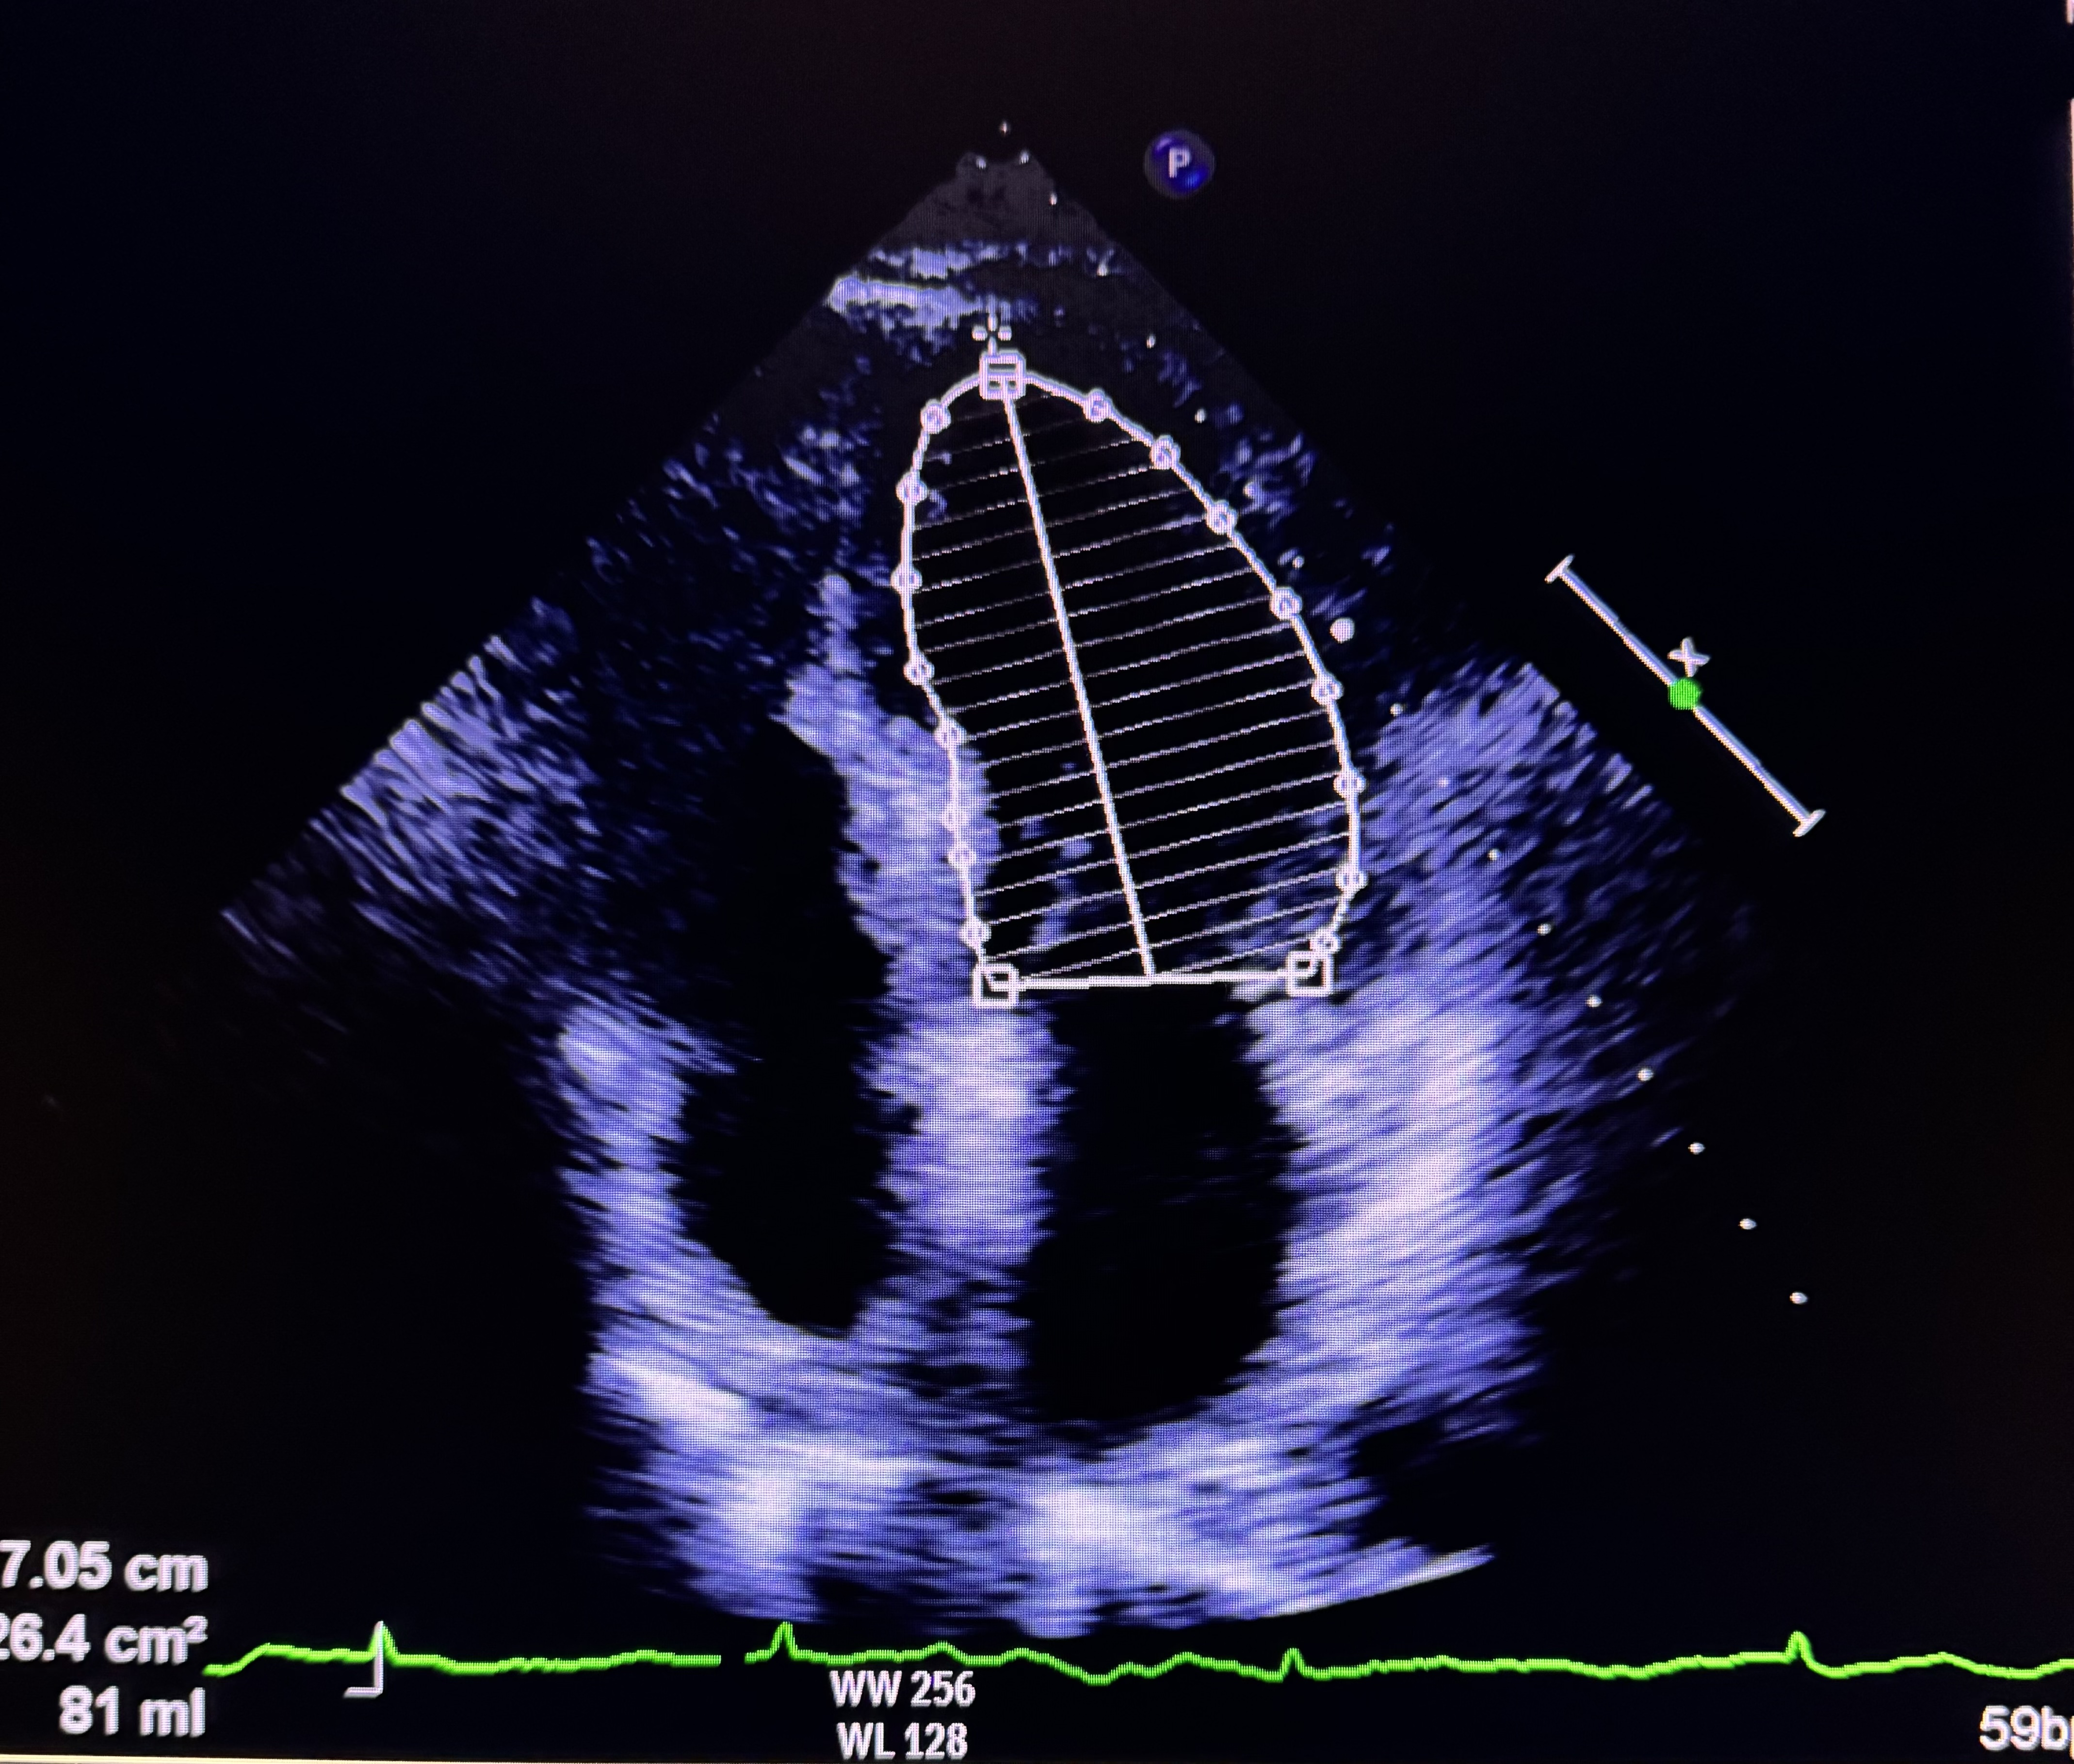

Relevant Test Results Prior to Catheterization

Cardiac Hs troponin was normal (20.4). Electrocardiogram demonstrated sinus rhythm 65 beats/min with isolated T inversion on lead IIIEchocardiogram demonstrated normal left ventricular systolic function with ejection fraction of 70%. Diastolic function corresponded with grade 1 dysfunction and no wall motion abnormalities. Her left ventricular size was normal with no evidence of mechanical complication of acute coronary syndrome. These informations led to the diagnosis of unstable angina